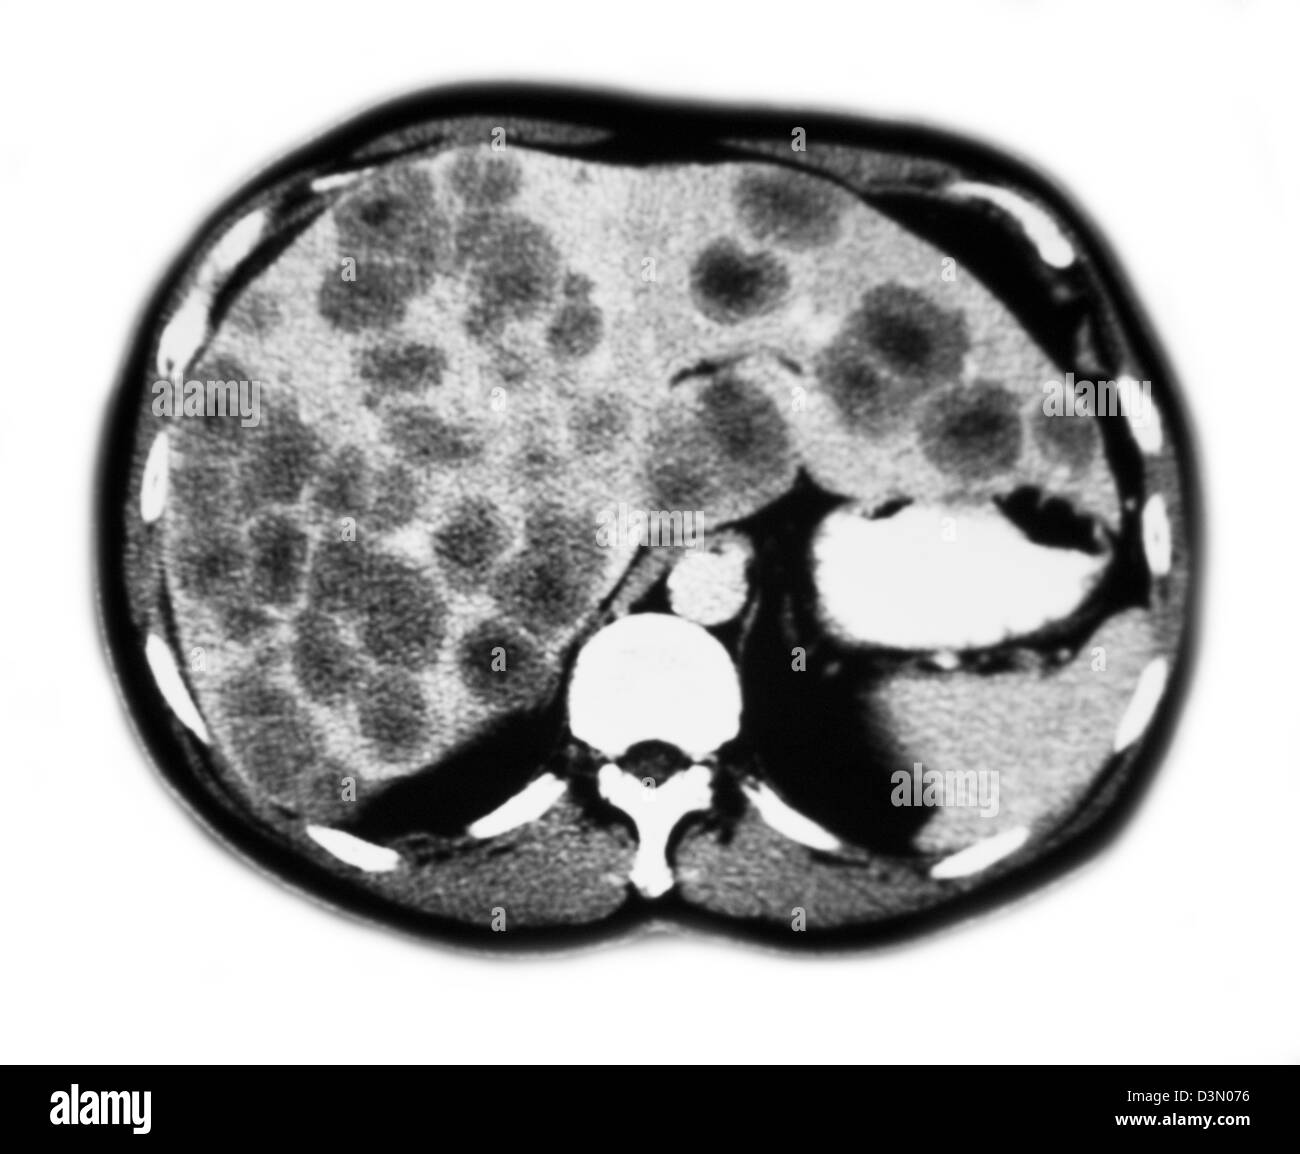

CT scan slices showing extensive metastatic liver cancer Stock Photo …

MEDICAL ULTRASOUND / LIVER METASTASIS

Diagnostic Value of Ultrasound in Metastatic Liver Cancer | Abdominal Key

C. Metastatic tumor in the liver seen in abdominal ultrasound …